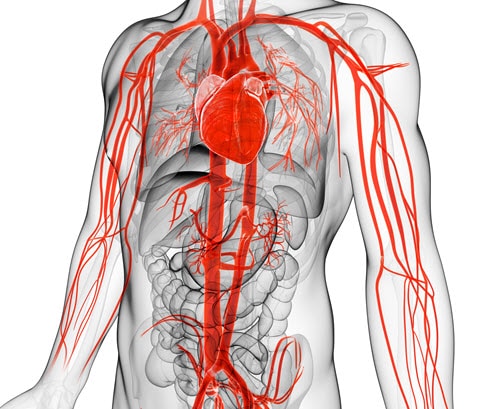

AORTIC ANEURYSM

The aorta runs from the heart through the center of the chest and abdomen. It’s the main blood vessel that brings blood to the abdomen, pelvis, and legs. An abdominal aortic aneurysm (AAA) is a life-threatening condition that occurs when the vessel enlarges, putting it at risk of bursting. Men are 4-15 times more likely to develop an AAA than women

Learn more about AAA. To learn more about our packs, wires, and other cardiac products, please visit our Merit Vascular page.

MERIT PRODUCTS

HEART ATTACK

A heart attack, also known as a myocardial infarction, occurs when heart muscle doesn’t receive enough blood. As time passes without receiving treatment, the more damage is done to the heart. The main cause of a heart attack is coronary artery disease (CAD). Researchers have found that throughout life, men are about twice as likely as women to have a heart attack.

Learn more about heart attacks. Explore our Cardiac Portfolio, including our radial sheaths, catheters, wires, and compression devices.

MERIT PRODUCTS